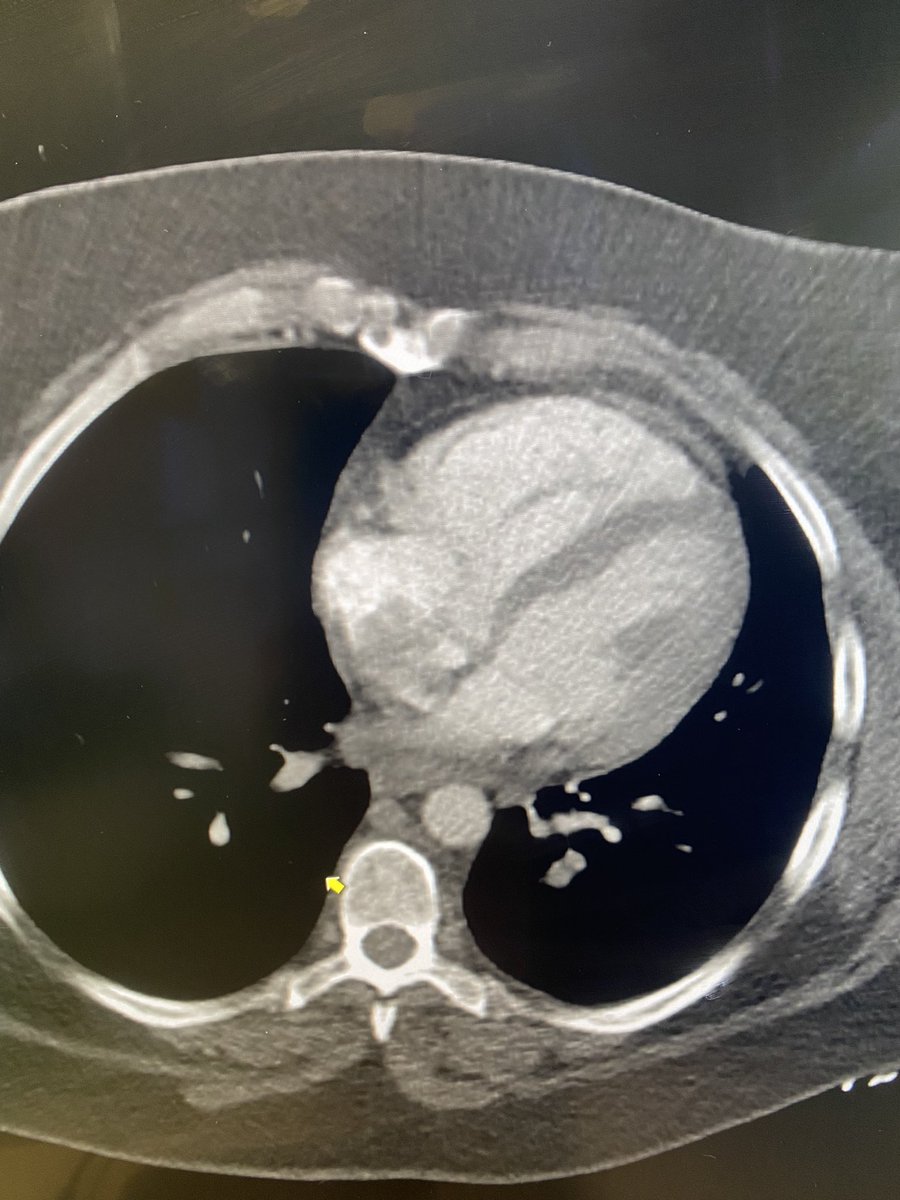

.@LucasRCmd, MPH; @HiroSparks, MD; Kara E. Masterson, MSN, NP; Scott J. Genshaft, MD; @AdamPlotnik, MD; and Siddharth A. Padia, MD, contributed to this open access article. See what they've been working on! brnw.ch/21wPx6v